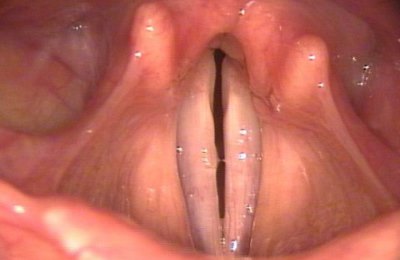

В стационаре, пациенту можно сделать ларингоскопию (прямую и непрямую), бронхоскопию.

Другие эндоскопические методы, с помощью которых можно определить степень поражения, причину патологического состояния, ширину голосовой щели.